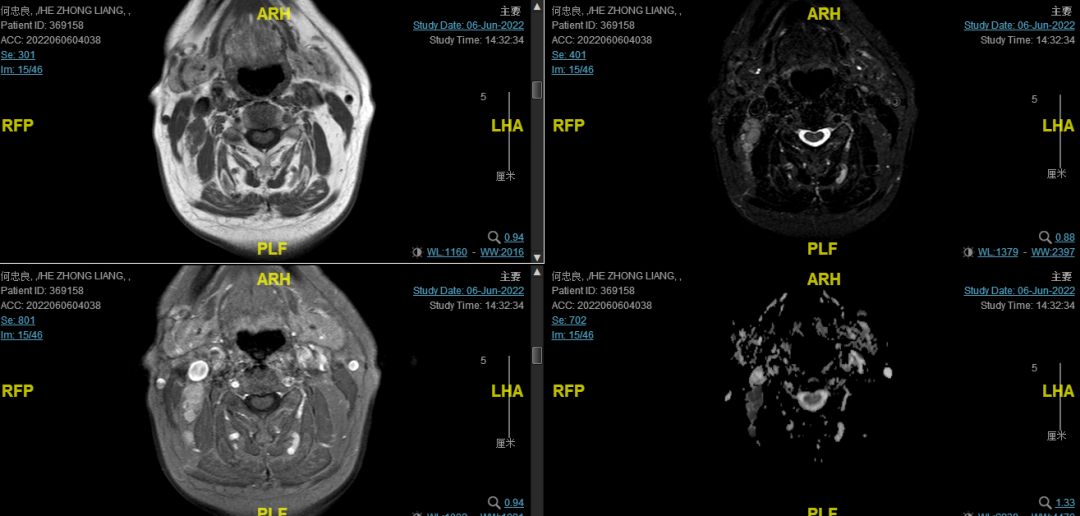

后患者至江苏省肿瘤医院放疗科就诊,2022-06-06完善头颅MR检查:

修正诊断:鼻咽癌T3N1M0,Ⅲ期。

2022-08-05(放疗近结束)复查MR,疗效评价:CR。鼻咽部肿物及咽后转移淋巴结颈部转移淋巴结均达到CR。